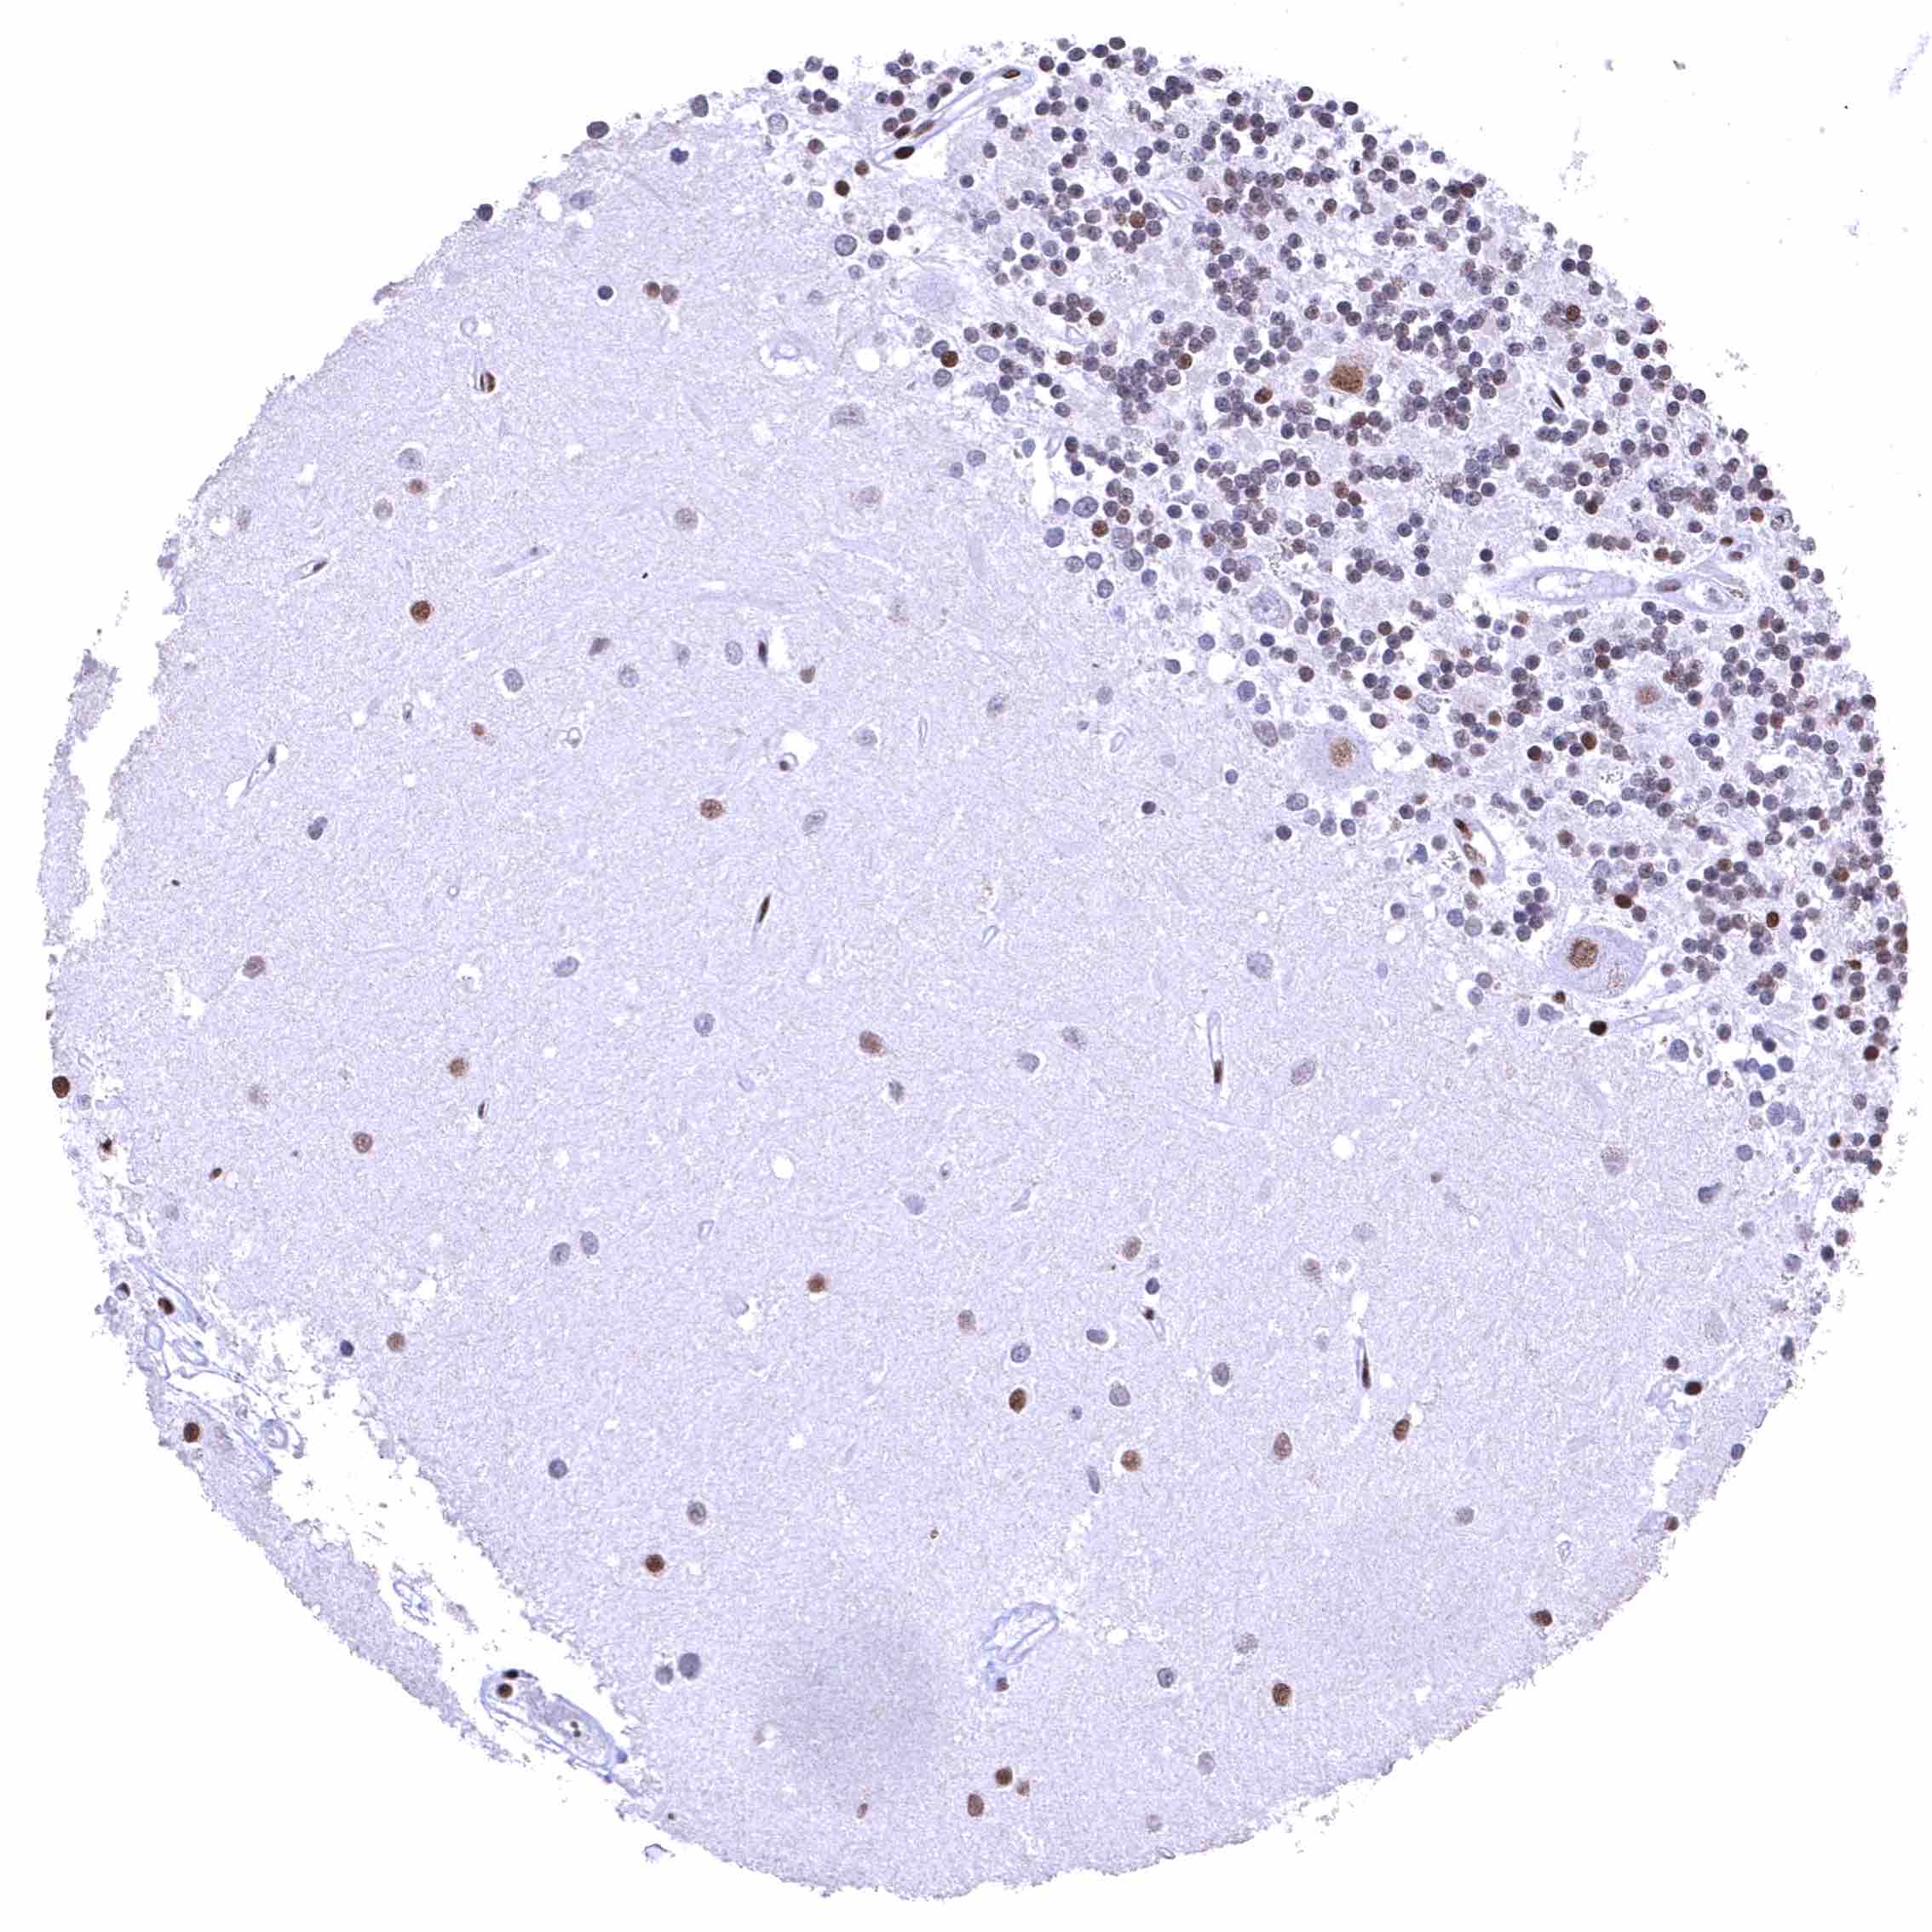

Cerebrum, grey matter – BRD4 staining is strong in glia cells but low or absent in neuronal cells.